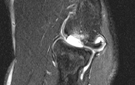

Weitere zusätzliche Informationen insbesondere über den Reizzustand des Weichteilgewebes können eine sonographische und auch eine kernspintomographische Untersuchung bei unklaren Befunden erbringen. Manchmal liegt hier bereits ein teilweiser Einriss der Handgelenksstrecker vor (Extensorendefekt).

Zusätzlich kann durch einen Unfall oder chronisch wiederkehrende Belastungen eine Schwäche des radialen Bandapparates am Ellenbogengelenk vorliegen. Diese Instabilität - auch postero-laterale Rotationsinstabilität (PLRI) genannt - führt dann zu einer chronischen Überbelastung der Extensoren. Das genaue Ausmaß einer PLRI lässt sich klinisch nur unzureichend feststellen. Im Rahmen einer Arthroskopischen Operation kann durch spezielle Manöver und Tests das Instabilitätsmuster nachvollzogen werden. Im Falle einer relevanten Instabilität sollte eine Bandplastik des geschwächten radialen Bandapparates in Betracht gezogen werden. Wir verwenden hier in der Regel ein Transplantat, welches aus der gleichseitigen Trizepssehne am Oberarm entnommen wird.